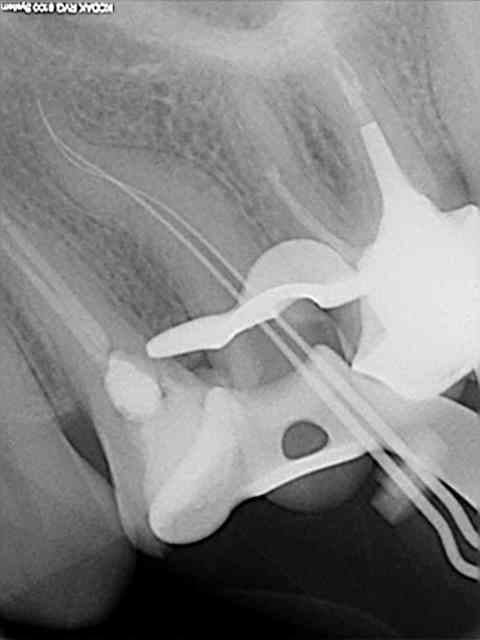

Une des premières fois que j'ai utilisé un contre-angle avec localisateur intégré.

Je me suis cru à l'abri avec le contrôle du torque sur l'instrument en temps réel.

Les diodes se sont alummées au début de la descente dans le canal et j'ai voulu continuer à avancer avec l'instrument en rotation malgré un cathétérisme manuel pas réalisé sur la totalité du canal.

Fracture , puis initiation de fausse route en essayant de passer à coté manuellement.